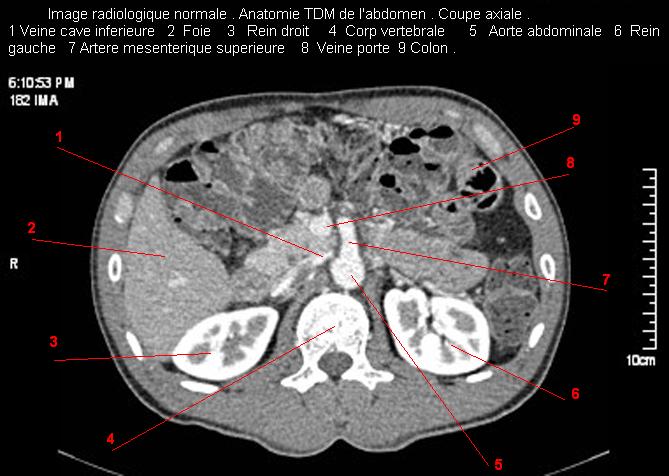

Image radiologique TDM normale de l'abdomen et tube digestif en coupe axiale ( CT scanner )  :

Coupe axiale     Coupe frontale      Coupe  sagitale